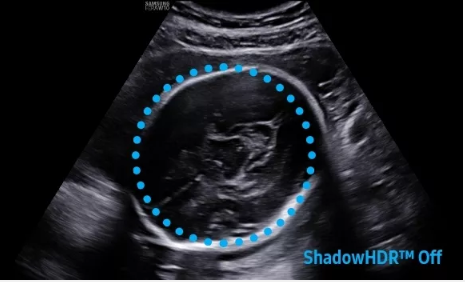

2D成像方面,Hera i10集成了包括ShadowHDR?、HQ-Vision?、ClearVision等多項具有三星“血統(tǒng)”的技術(shù),加強(qiáng)了圖像的陰影抑制、減少偽影、緩和模糊區(qū)。